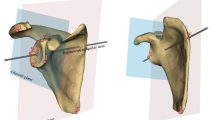

Current clinical practice often relies on MRI arthrograms (MRAs), where contrast is injected into the joint to enhance visualization of labral structures15,16. The improved visualization of intra-articular structures is apparent in Fig. 1, which depicts the same Bankart lesion on an MRA and a standard (non-contrast) MRI. While MRAs achieve sensitivity and specificity rates of 74–96% and 91–98%, respectively17,18,19, they are invasive, more expensive than standard MRIs, and associated with patient discomfort and risks such as allergic reactions and joint infections15,20,21,22,23,24. Standard (non-contrast) MRIs, on the other hand, are non-invasive and more widely available but are significantly less reliable for detecting Bankart lesions, with reported sensitivity rates as low as 52–55%25,26. This disparity underscores the urgent need for non-invasive diagnostic approaches that can match the diagnostic accuracy of MRAs while reducing patient burden and healthcare costs.

Grad-CAM33 visualizations highlight regions relevant to a model’s predictions. Figure 5 presents Grad-CAM heatmap visualizations for the axial view for four representative cases: an MRA without a tear, an MRA with a Bankart lesion, a standard MRI without a tear, and a standard MRI with a Bankart lesion. For all heatmaps, annotations highlight the anterior labrum, placed by a shoulder/elbow fellowship-trained orthopedic surgeon. The model attended to the relevant portions of the image, as determined by the surgeon, on all four cases.

Cases with and without Bankart lesions are presented. The model correctly classified all four cases. White circles highlight the anterior labrum (the region of interest), annotated by a shoulder/elbow fellowship-trained orthopedic surgeon. Heatmaps indicate regions most influential to the model’s prediction, with warmer colors (red/yellow) signifying higher relevance.

The Grad-CAM visualizations in Fig. 5 for the MRAs demonstrate focused activation within the anterior labrum for both the no-tear case and Bankart lesion case. For the no-tear MRA, the area of highest activation is in the anterior-inferior labrum region, but there is an additional lesser area of activation near the posterior

labrum. In the Bankart lesion case, there is strong overlap between the activation and the surgeon-annotated region highlighting the tear, likely indicating that the model successfully identified the pathological features associated with the tear. For the standard MRIs, the Grad-CAM visualizations show less localized activation compared to MRAs, with several peripheral areas of minor activation near the image edges in both cases. This reduced specificity in the activation maps may result from the lower visual clarity of labral structures on standard MRIs due to the lack of intra-articular contrast. Additionally, as noted in Table 3, the standard MRIs had a significantly lower percentage of 3.0 T exams (i.e. higher proportion of lower quality 1.5 T exams)—suggesting that the lower average image quality in the standard MRI group may also have contributed to the less focused heatmap. Although the standard MRI dataset was larger overall (335 MRIs vs. 251 MRAs), it contained far fewer positive cases (8.6% vs. 31.9%), creating substantial class imbalance. This imbalance likely limited the model’s ability to learn localized features, leading to more diffuse activations. The broader activations likely reflect a combination of these factors, underscoring the need for cautious interpretation. For the no-tear standard MRI case, the heatmap shows the highest activation in the anterior labrum, suggesting that the model still prioritizes this region as a key diagnostic feature, even in the absence of pathology. For the Bankart lesion case, the anterior labrum remains the area of highest activation, but the heatmap also strongly highlights additional regions within the joint space. Unlike for the MRA, the annotating surgeon noted no obvious tear characteristics for the standard MRI with a Bankart lesion. Consequently, the additional highlighted regions in the model’s heatmap may reflect subtle imaging cues associated with the tear that are not easily discernible to human observers. This suggests that the model may capture features indicative of the tear that are challenging for radiologists or surgeons to detect on standard MRIs due to the lack of intra-articular contrast.